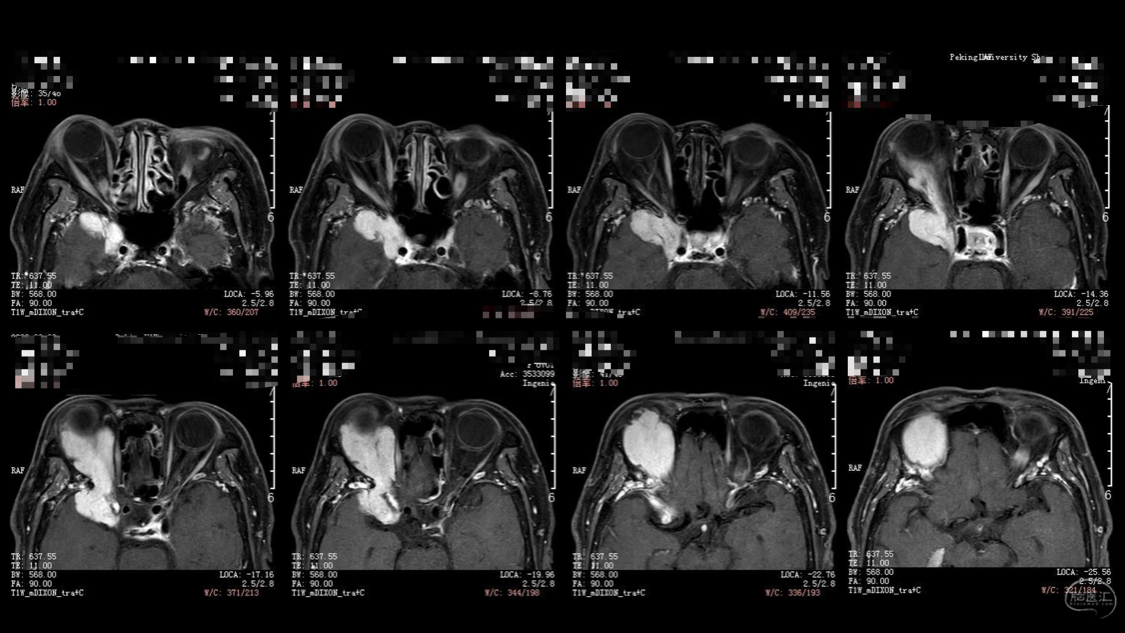

陈保东教授手术作品-右眶内及海绵窦旁孤立性纤维瘤